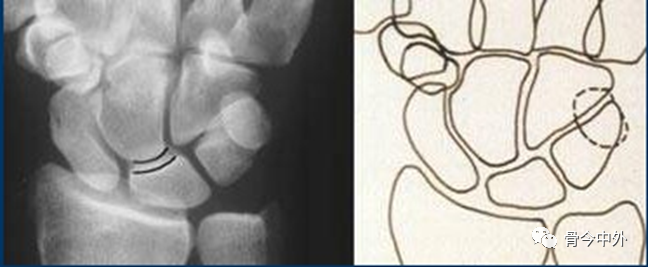

3.腕骨弧线

Gilula 提出三个平滑的弧形勾画出近侧列和远侧列腕骨。弧 I 把舟骨、月骨和三角骨近端关节面连在一起;弧 Ⅱ 勾画出上述骨远端凹面;弧 Ⅲ 由头状骨和钩骨远端凸面所形成。

图16腕骨弧。在正常腕关节背掌位X线片上3个平滑的弧线勾画出近侧列和远侧列腕骨。